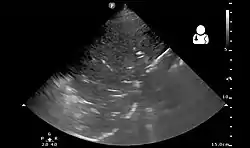

Lung ultrasound may also be useful in helping to make the diagnosis.[67] Ultrasound is radiation free and can be done at bedside. However, ultrasound requires specific skills to operate the machine and interpret the findings.[33] It may be more accurate than chest X-ray.[68]